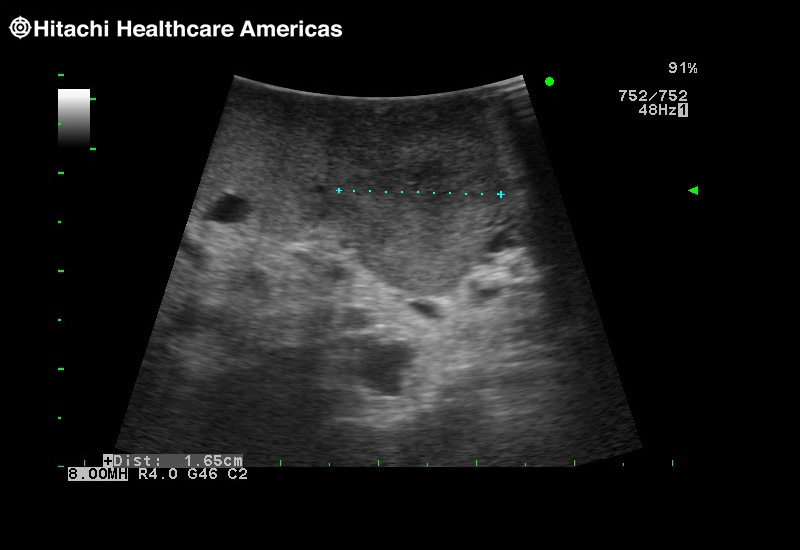

Superior guidance for all applications

Fujifilm Healthcare Americas is committed to designing tools that help surgeons navigate inside the human body and provide the necessary information to immediately make critical surgical decisions.

Fujifilm Healthcare's dedication to Surgeons provides outstanding ultrasound technology, professional support and the specialized tools necessary to best perform comprehensive real-time ultrasound imaging in Breast Surgery, General Surgery, Laparoscopic Surgery, Neurosurgery, Robotic Surgery and Surgical Oncology.

Recognized for our outstanding image quality, outstanding system reliability and intuitive use of cutting edge technology, Fujifilm Healthcare remains the standard in the field of Surgery.

Recognized for our outstanding image quality, outstanding system reliability and intuitive use of cutting edge technology, Fujifilm Healthcare remains the standard in the field of Surgery.